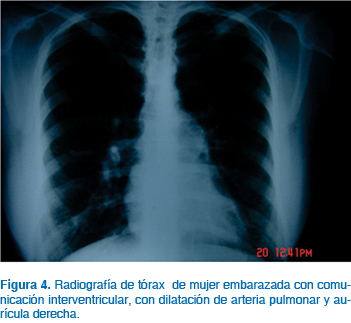

Los defectos del tabique interventricular (DTIV), o también denominado comunicación interventricular, son un grupo de enfermedades que representan la cardiopatía congénita más frecuente; algunos estudios la reportan hasta en un 30% del total de enfermedades congénitas cardiacas identificadas en adultos, con un rango de 16 a 50%13 (Figuras 4 a 6). Las mujeres con comunicación interventricular pequeña, sin hipertensión arterial pulmonar y sin lesiones asociadas no tienen mayor riesgo cardiovascular para el embarazo. Las mujeres con hipertensión arterial pulmonar deben recibir consejería previa al embarazo. El embarazo es generalmente bien tolerado, sin mortalidad materna y sin morbilidad significativa materna o fetal, aunque el cortocircuito de izquierda a derecha se incrementa con el aumento del gasto cardiaco durante el embarazo. Las mujeres con grandes cortocircuitos y presencia de hipertensión arterial pulmonar pueden presentar arritmias, disfunciones ventriculares y la progresión de la hipertensión arterial pulmonar.6,10